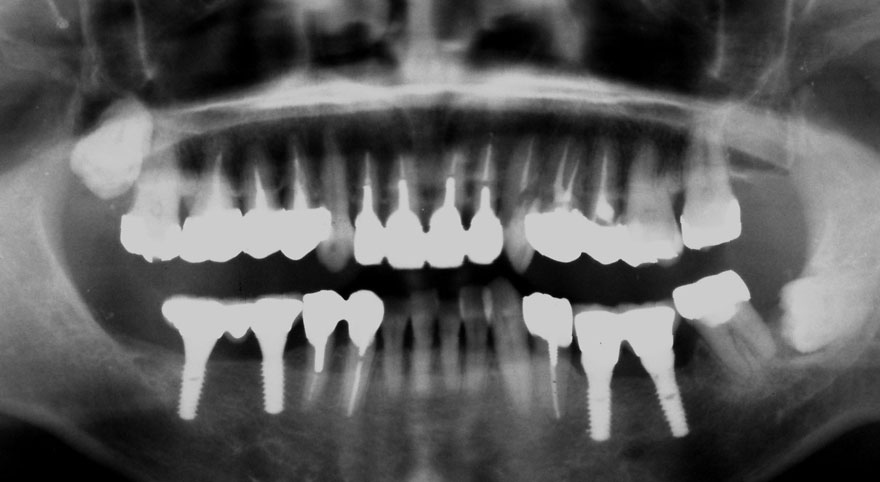

初診時 42歳 男性 平均歯槽骨喪失量:5.30mm

22年後 64歳

平均歯槽骨喪失量:5.554mm

22年間喪失量:-0.24mm

年間喪失速度:-0.01mm

(ケア頻度:1.07ヵ月ごと)